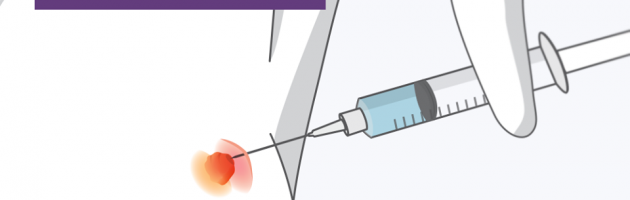

Biópsia mamária: eu vou sentir dor?

Saiba como é feita a biópsia de tireóide